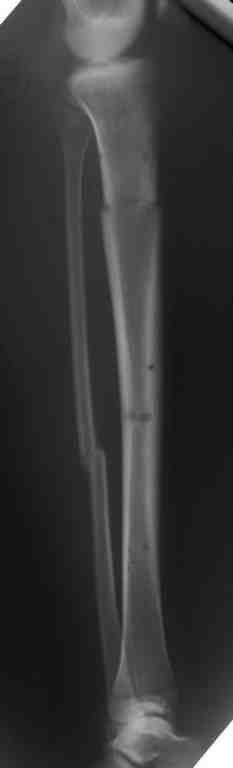

В верхнем ряду показаны рентгенограммы до, после коррекции и после снятия аппарата Илизарова. On the upper row the X-rays of lt leg before correction, after correction and after apparatus removal have been showed.

В нижнем ряду представлены два снимка после коррекции деформации правой голени. Видно, что качество коррекции не зависит от квалификационного наложения аппарата Илизарова, что было специально произведено для проверки работы программы. Lower two X-rays – rt leg after deformity correction. As you can see the quality of correction does not depend of placement of Ilizarov Apparatus